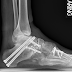

First things first, I had surgery the other day on my left foot. The surgeon cut the tendons in my four smaller toes to get them to lay down flat. Compared to the other surgery I had previously, this recovery is quite benign. For those of you considering something to straighten your toes, I highly recommend it.

And then there is the fear that I hold in my heart about my CMT. I've had surgery on one foot and it has been such a remarkable change in my life. I'm so excited to have surgery on the other foot as soon as time permits, but I am still terrified for the future. CMT is so unpredictable that I really have no way to picture the future of my life. Will my mobility suddenly get worse? Or will the damage stop and I'll stay exactly how I am for the rest of my life?